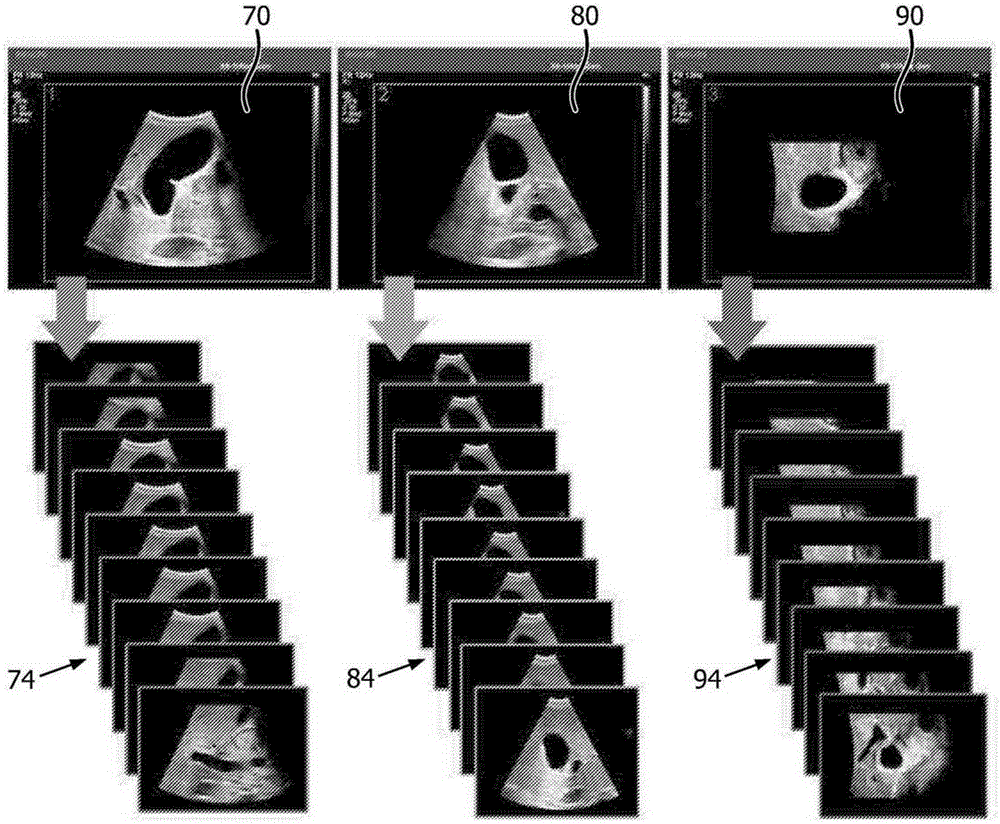

体积超声图像数据重新格式化为图像平面序列